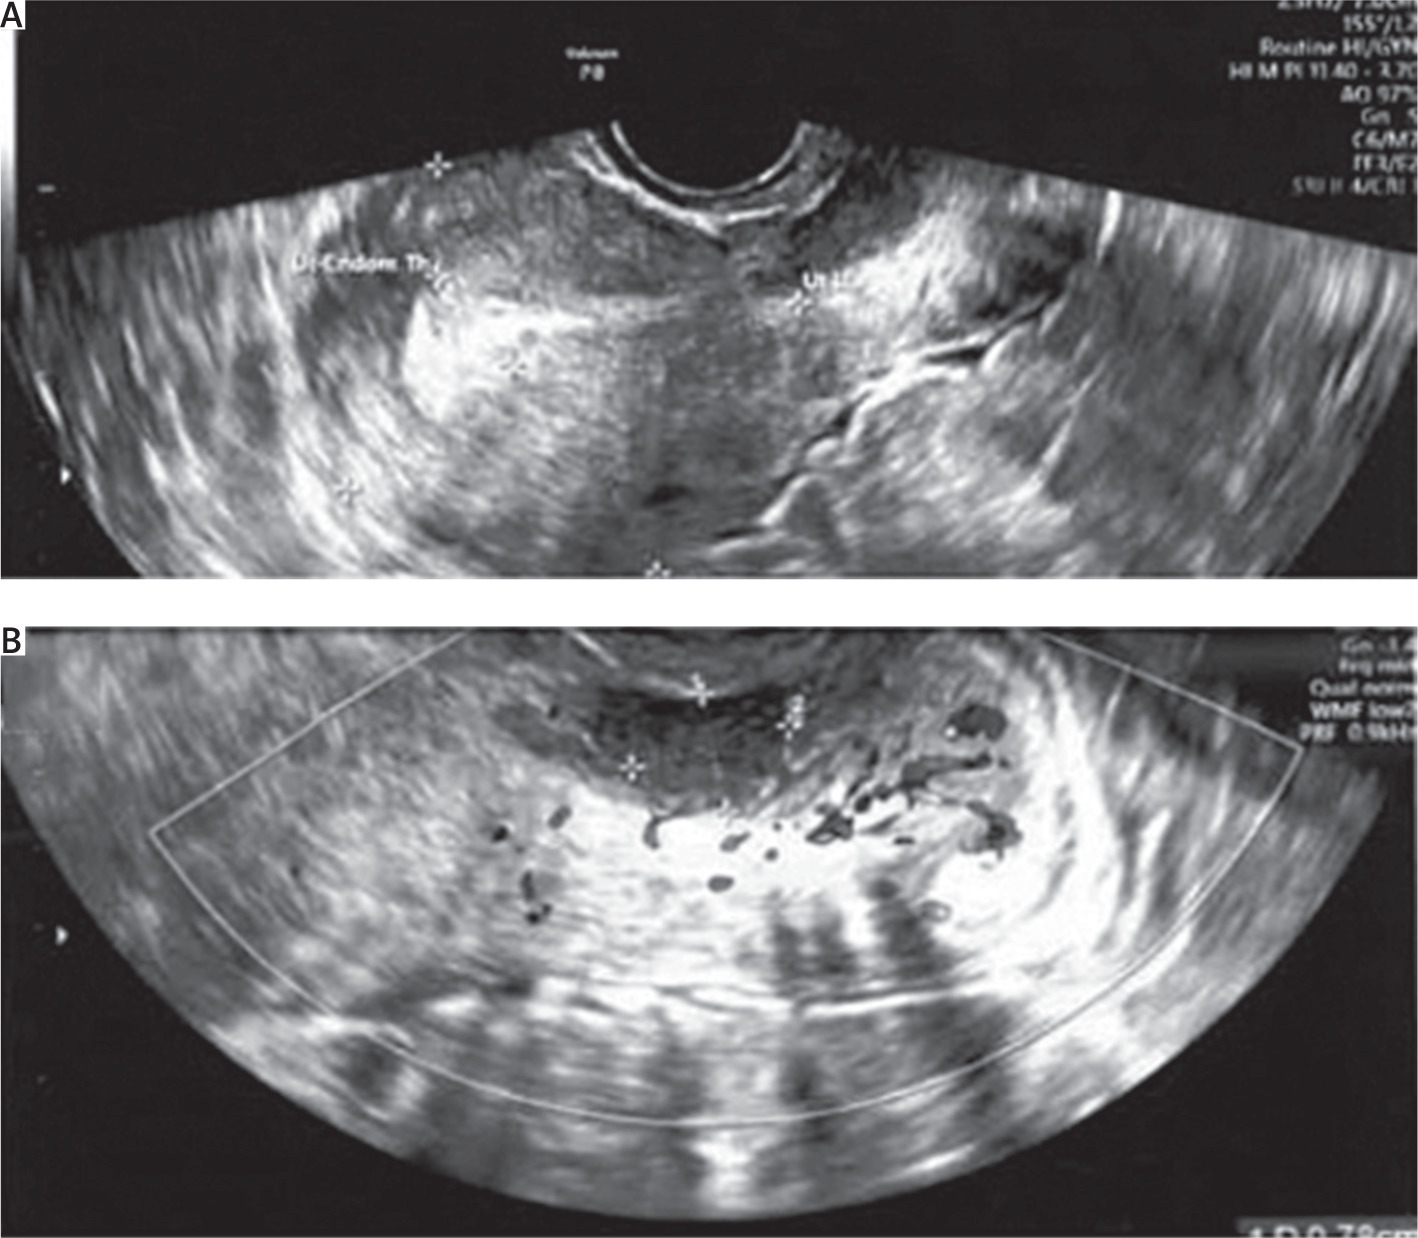

The pathological results confirmed a low-grade adenosarcoma. Macroscopic examination of the specimen revealed a 3 cm long cervix, a 4.5 × 4 cm area with “erosion” in the external opening, with a whitish infiltration reaching the ectocervix and in the area of the internal opening. Body of the uterus: 6.5 × 5 × 6.5 cm. Endometrium was macroscopically normal, 3 mm in thickness, with a slit-like cavity. The cervical tumour macroscopically did not invade the body of the uterus. Microscopic examination results showed the neoplastic tissue found in the vaginal portion of the cervix and cervical canal. Maximum depth of stromal invasion was assessed as 15 mm, maximum lesion size – about 25 mm. The minimum radial margin in the cervical canal was 7 mm. The minimum excision margin from the vagina was 11 mm. The cervical surface was covered with normal paraepidermoid epithelium. The endometrium was in the secretory phase, and traces of adenomyosis were found. The parametrium was free from any neoplastic infiltration. Both ovaries and fallopian tubes were found to be of normal histological structure. Sampled, enlarged lymph nodes were assessed, and no cancer metastases were detected. The neoplasm was classified as stage: pT1b1N0, FIGO IB2 (Figure 2).

Figure 2

Microscopic examination. A) The histopathological analysis reveals glandular structures lined by metaplastic mucinous epithelium, lacking cellular atypia or mitotic activity. Additionally, the stromal component consists of spindle cells organized in sheet-like arrangements. B) The borderline between healthy and cancerous tissue